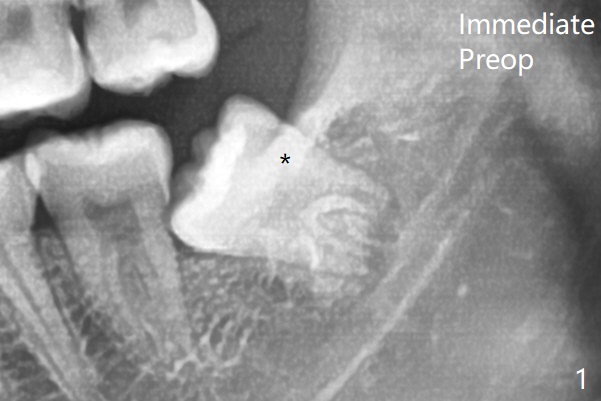

20岁女由于右下智齿疼痛就诊,诊断后,要求先拔除两个下颌智齿。外斜嵴好像跨越牙槽窝远中(图一:*),拔除似乎没有缩短外斜嵴长度(图二:*),牙槽窝放置胶原塞。